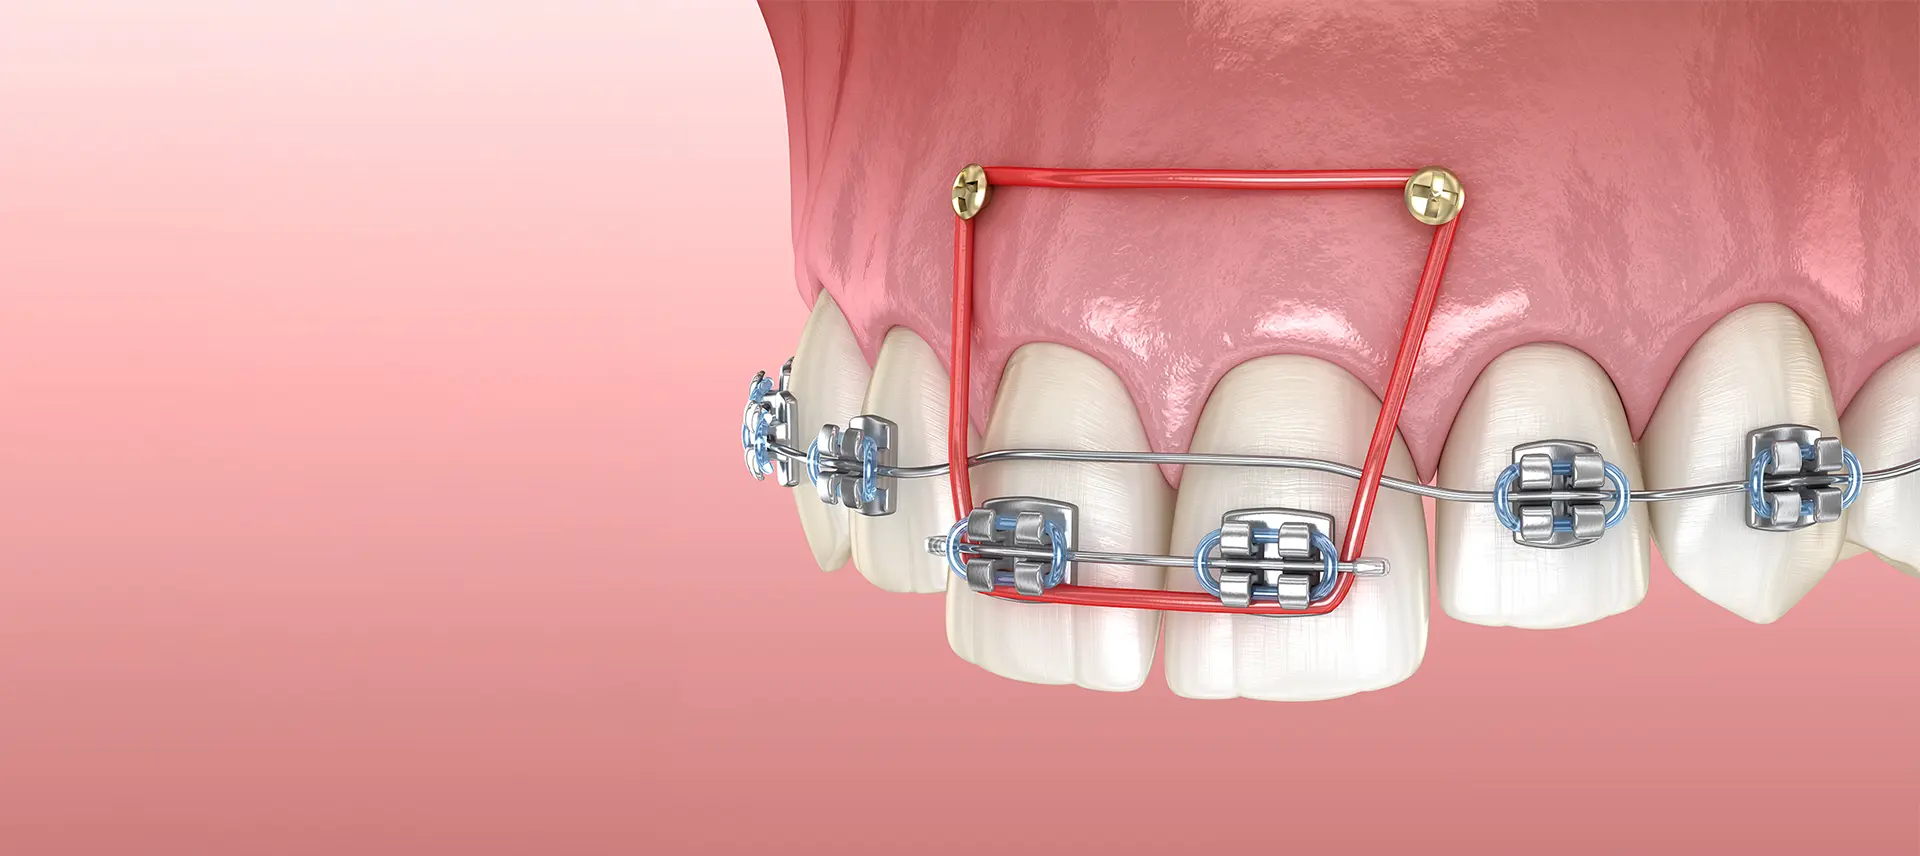

歯科矯正用アンカースクリューを用いた矯正治療は、歯科矯正用に開発された小さいアンカースクリューを顎骨に埋め込み、これを固定源として歯を動かします。

固定源を得ることで、今までの矯正治療では動かすのが難しかった方向にも歯を動かせるようになり、治療期間の短縮や、顎骨を切らないで治療できる選択肢が広がりました。また、非抜歯矯正の可能性が高くなったり、顎間ゴムやヘッドギアといった補助装置の使用頻度の低減によって、患者さまのご負担を軽減できるメリットもあります。

歯科矯正用アンカースクリューは、歯を動かす目的で作られているため、歯の移動方向・量などに合わせて、さまざまな部位に埋め込めるようになっています。